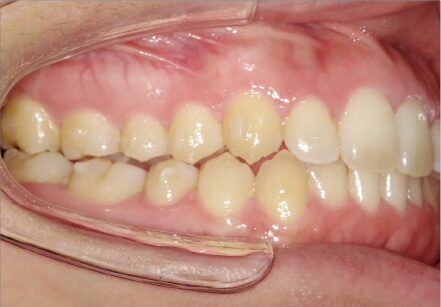

叢生の症例

41歳

/

女性

相談内容

正中がズレている。傾いている歯がある。

カウンセリング・診断結果

叢生・アレルギーなし・ext、IPR、アタッチメント、ミニスクリュー、ゴム掛け承諾

治療内容・方法

全額アライナー矯正・左下7セラミックはそのまま進めていく

術後の経過・現在の様子

クリアライナー使用

治療のリスク

痛み・歯根吸収・歯肉退縮・虫歯・後戻り

費用・治療期間

880,000円、1年9ヶ月

トレーニングなど